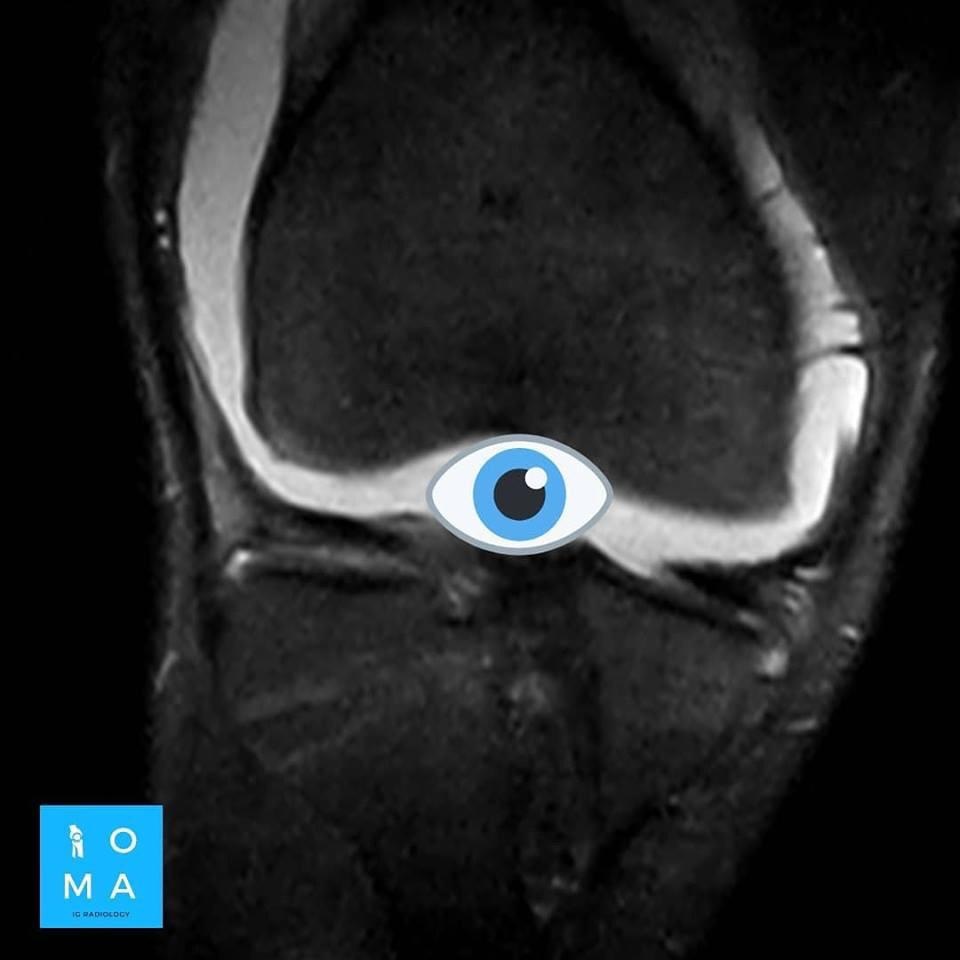

La evaluación hepatica entre Adenoma y HNF por resonancia magnética y su diferenciación con hepatocarcinoma puede ser difícil en ciertos casos aún, con el uso de contraste hepato especifico.

Se presenta caso de paciente de la 3a década, que en su embarazo se diagnostica con sospecha de adenoma y posterior al embarazo se realiza estudio de control contrastado para su mejor diferenciación.

En la evaluación con medio de contraste, se evalúa la relación arterial y de las venas, esto puede servir para buscar la arteria central relacionada con la hiperplasia nodular focal o bien, para evaluar la relación con las estructuras vasculares que son muy importantes para el planeamiento quirúrgico .

en este caso, aún cuando los hallazgos son atípicos tanto para hiperplasia nodular focal como para adenoma, nos inclinamos hacia el diagnóstico de adenoma debido a los antecedentes de la paciente, el tamaño de la lesión, el área de sangrado, el contenido de grasa.